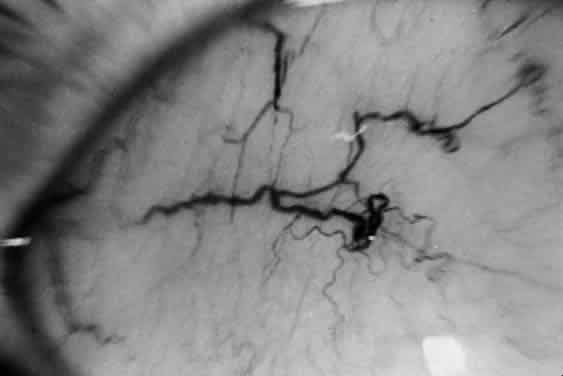

The principal ophthalmologic manifestation of MPS II is progressive retinal degeneration with attendant impairment of vision.21,51 Night vision problems and visual field defects are common. The disorder may lead to blindness. The fundus signs include retinal pigmentary changes, sometimes spicule formation, retinal arteriolar attenuation, and optic disc pallor. The ERG is usually reduced or extinguished21,22,52; in some cases it is normal.22 In addition, bilateral epiretinal membranes with tortuosity of the retinal vessels has been reported as an unusual finding in two brothers with Hunter syndrome type B.53

Swelling of the nerve head is a frequent finding in Hunter syndrome; it may be due to increased intracranial pressure or mucopolysaccharide deposition in and around the optic nerve.44,54–56

Goldberg and coworkers reported the occurrence of papilledema and abducent palsy secondary to the increased intracranial pressure of hydrocephalus in a child with Maroteaux-Lamy syndrome.75 In addition, they documented tortuosity of the retinal vessels not only in the child with papilledema but also in her siblings, whose optic discs were normal. Sheridan and Johnston also documented the occurrence of papilledema secondary to hydrocephalus in Maroteaux-Lamy.56